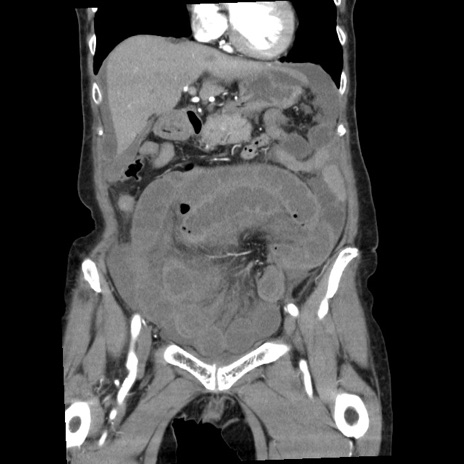

症例1(冠状断像)

【症例】80歳代女性

【主訴】腹痛

【現病歴】8時間前から腹痛あり来院。

【既往歴】糖尿病、脂質異常症、子宮体癌にて子宮全摘術

【身体所見】意識清明・会話良好だが腹痛で苦悶様、全腹部にわたって反跳痛と圧痛あり

【データ】WBC 13600、CRP 0.14、LDH 224、CK 90